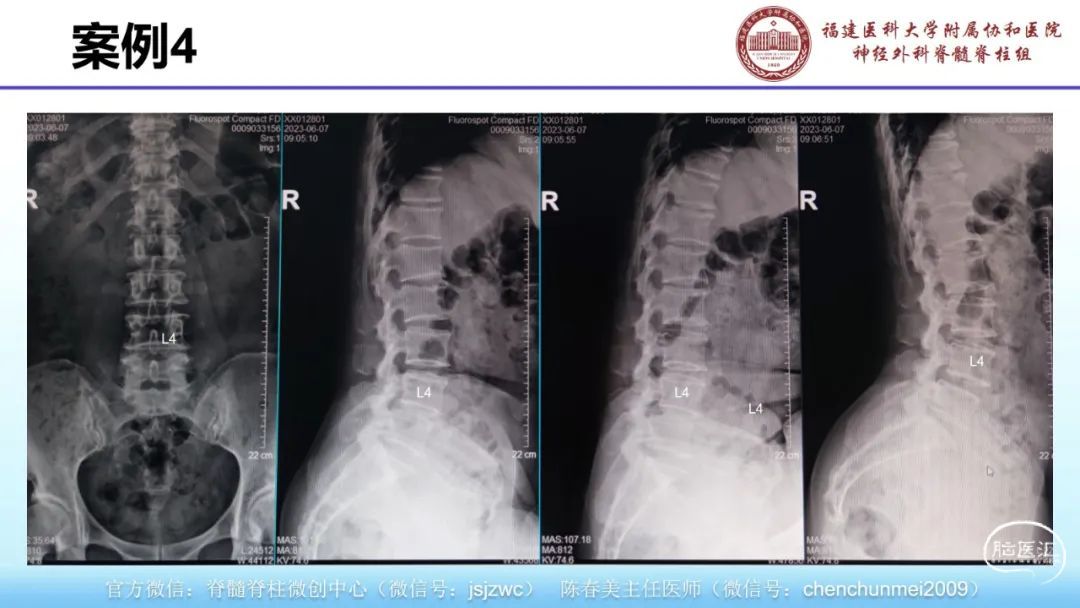

在手术室观摩6-8台显微镜微通道、神经内镜治疗脊柱脊髓疾病手术,包括颈椎病、腰椎病、椎管肿瘤等微创治疗等。